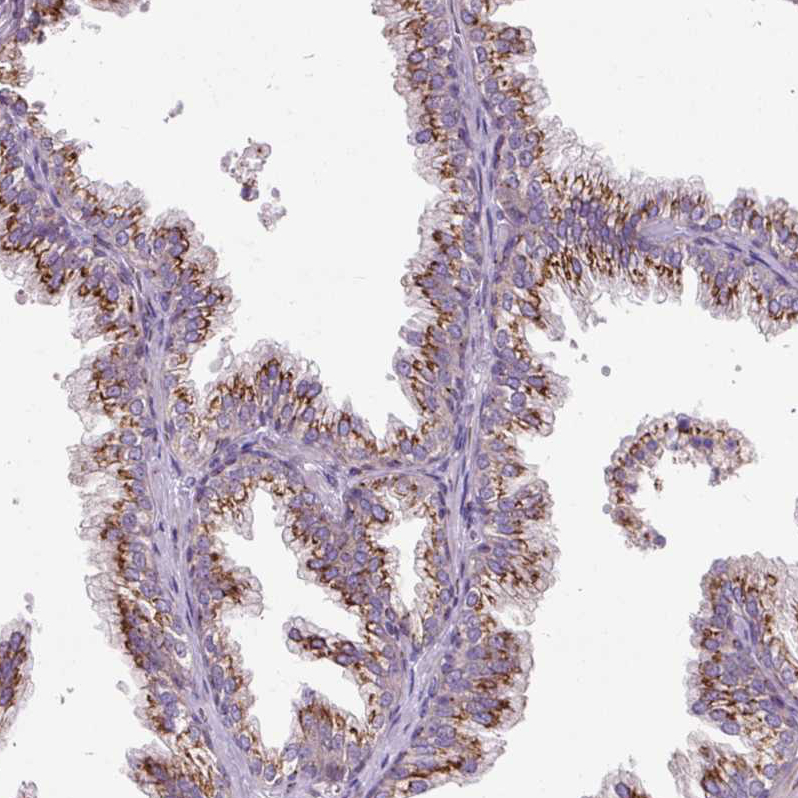

Immunohistochemical staining of human placenta shows strong cytoplasmic granular positivity in trophoblastic cells.